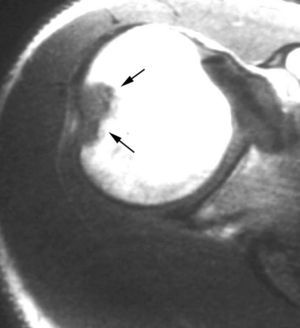

Lesiones por pinzamiento anterosuperior (anterosuperior impingement syndrome)

El síndrome de pinzamiento anterosuperior se produce durante el movimiento repetitivo de elevación anterior del brazo con rotación interna. En este síndrome se pueden producir lesiones de la polea reflectora (LGHS, TLB y LCH) así como del LG superior y de los tendones del supraespinoso y subescapular (fig. 33). Habermeyer et al29 han descrito cuatro tipos de lesiones por pinzamiento anterosuperior dependiendo de las diferentes estructuras afectadas.

Fig. 33.--Síndrome de pinzamiento anterosuperior (ASI). Resonancia magnética (RM) axial GRE (A) y coronal oblicua DP (densidad protónica) (B) que revela una rotura del ligamento glenohumeral superior (LGHS) (flechas en A) y una lesión SLAP (superior labrum anterior posterior) tipo II (flecha en B).

En general, este tipo de lesiones son semejantes a las lesiones que afectan al intervalo MR, con la diferencia de que las primeras son por lesión repetitiva y crónica, mientras que las segundas son por traumatismo agudo.